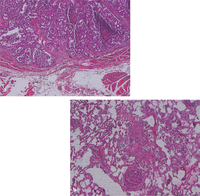

Большинство опухолей молочных желез у кошек происходят из эпителия желез и все строго являются аденомами или аденокарциномами, хотя последние часто относят к карциномам. Доброкачественные опухоли встречаются нечасто, из них наиболее часто встречается фиброаденома и редко встречаются простая аденома или папиллома протоков. Основным гистологическим типом опухолей молочных желез у кошек является простая аденокарцинома, происходящая из эпителия протоков молочных желез и альвеол (Изобр 6).Комплексные или смешанные опухоли, вовлекающие как протоковые, так и миоэпителиальные клетки редко встречаются у кошек, в сравнении с собаками, хотя они могут быть ассоциированы с более хорошим прогнозом (22,23) . У кошек карциномы могут быть тубулопапиллярными, солидными, решетчатыми или муцинозными, хотя переходноклеточная карцинома и смешанная карциносаркома также встречаются (24).

Изобр 6. Гистологическое исследование простой аденокарциномы молочных желез кошек. Срезы показывают инвазию первичной опухоли в мышцу (а), метастаз в легкие (b) с опухолевыми клетками в кровеносных сосудах и легочной ткани.